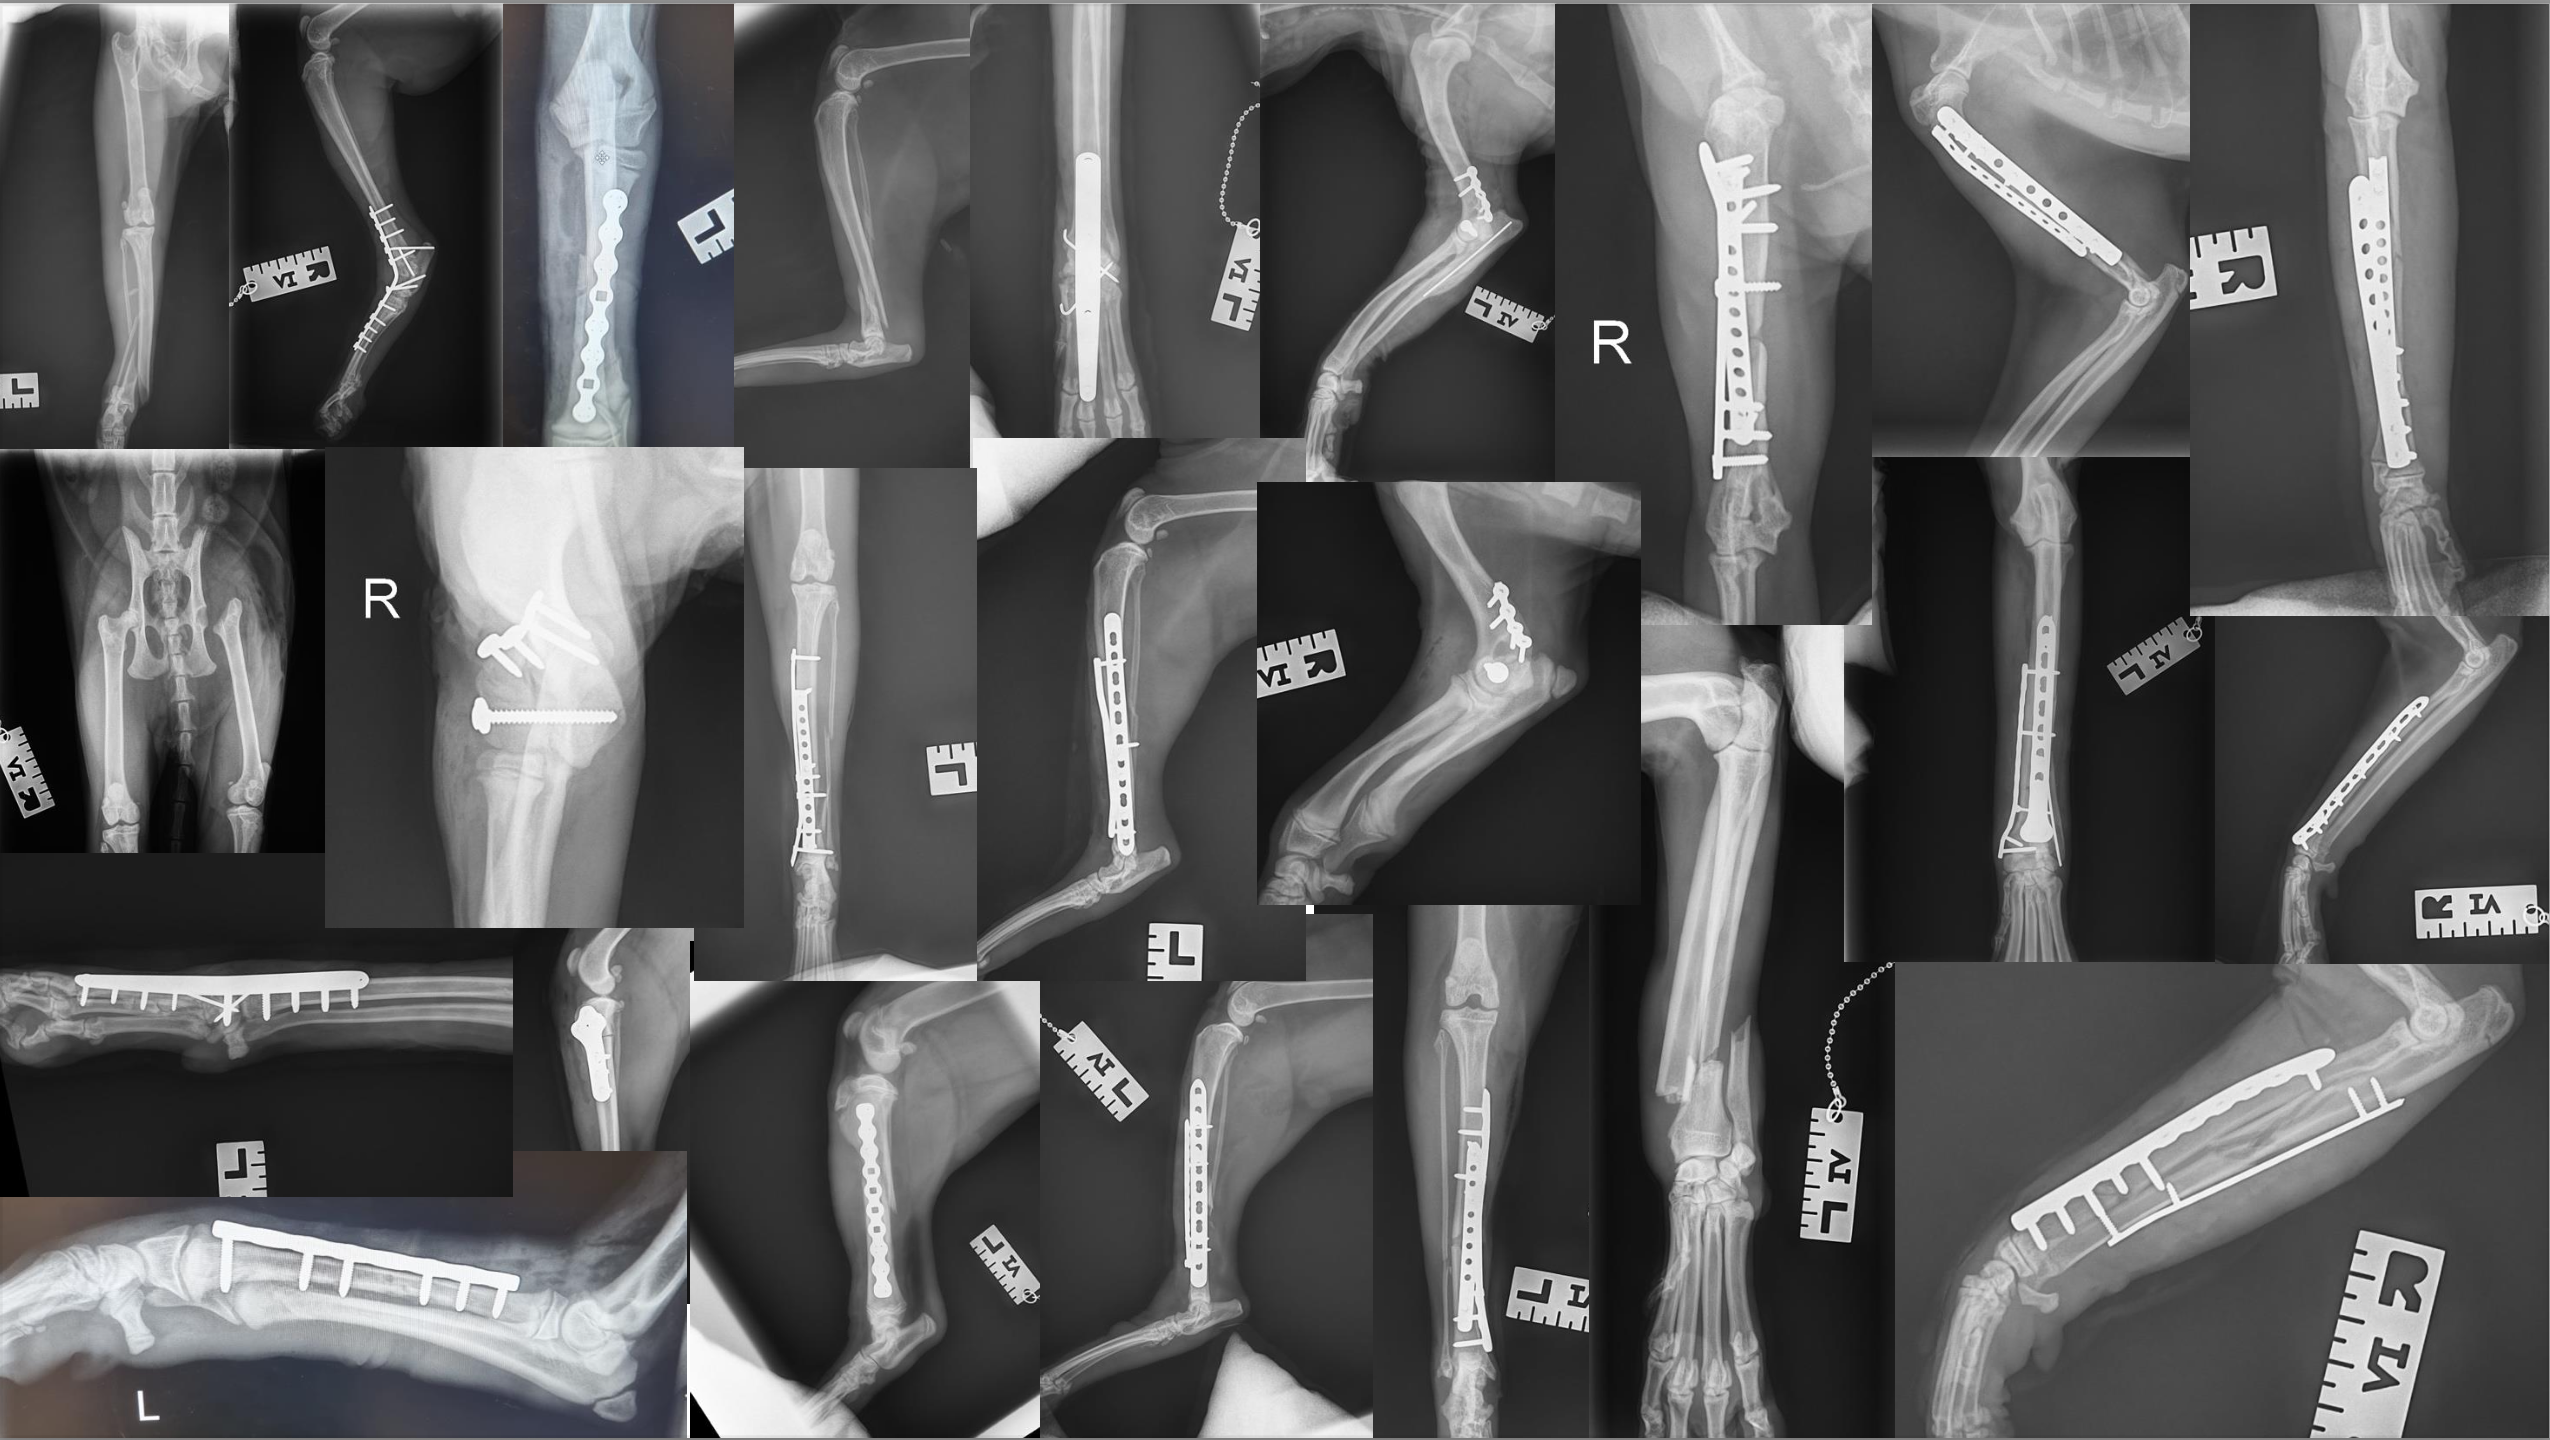

We fix dog and cat broken legs for low cost, fixed prices.

- We offer low-cost, fixed-price fracture repair

- Our surgeon, Simon, has 20 years’ experience and is an RCVS-registered advanced practitioner

- We have all the kit and know-how in the building

- We won’t cut corners with treatment – we will do everything we think your case needs